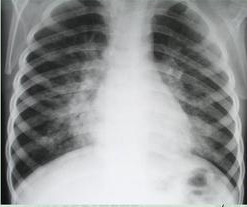

10月27日,上海浦东伊咏儿科送来了一份加急儿童胸片病例,童童因为咳嗽、间断发烧6天被父母送入上海伊咏儿科治疗,伊咏儿科马上安排童童拍了胸片,并迅速与上海全景医学影像诊断中心取得联系。通过全景“互联网医学影像云平台”将童童的病例资料以及影像资料上传,我院影像医生沈洁云诊断为支气管肺炎,快速出具影像诊断报告。医院接到诊断报告后迅速为童童安排了后续治疗,整个过程在30分钟内完成。这是上海全景医学影像诊断中心利用“互联网医学影像云平台”完成的首例远程协助诊断。

(童童的胸部CT)

上海伊咏儿科是与上海儿童医院中心(特诊部)合作的儿科专科门诊部,对诊疗各个关节的质量与安全进行严格把控,力求为广大儿童及家庭提供规范、安全的诊疗服务。此次远程影像诊断是上海全景医学影像中心与上海伊咏儿科首次利用互联网进行的远程影像诊断合作,伊咏儿科通过全景“互联网医学影像云平台”系统将童童的胸部CT影像上传,我院影像医生快速诊断,半小时内出具专业影像诊断报告,避免了童童父母去三甲医院预约专家排队挂号的奔忙,也节省了大量时间,使童童能够尽早得到有效治疗。